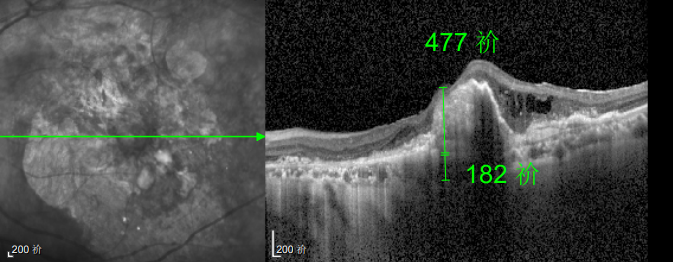

△規(guī)劃化治療后的左眼

幸運(yùn)的是,三年后的一次例行復(fù)查中,醫(yī)生通過(guò)眼底監(jiān)測(cè)及時(shí)發(fā)現(xiàn)林婆婆的右眼眼底病變問(wèn)題,確診為濕性老年性黃斑變性。得益于定期篩查的及時(shí)性,王曉波主任第一時(shí)間為她啟動(dòng)治療,最終成功將右眼矯正視力穩(wěn)定在0.8左右。